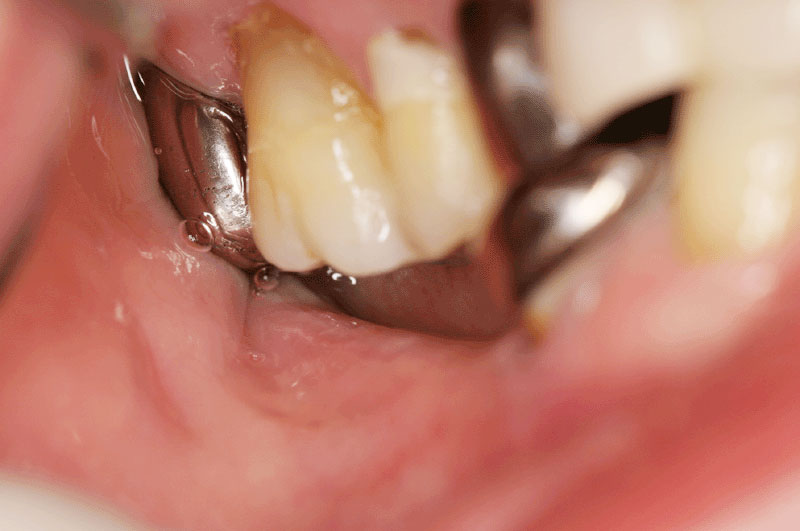

CASE 2 下の奥歯がない方